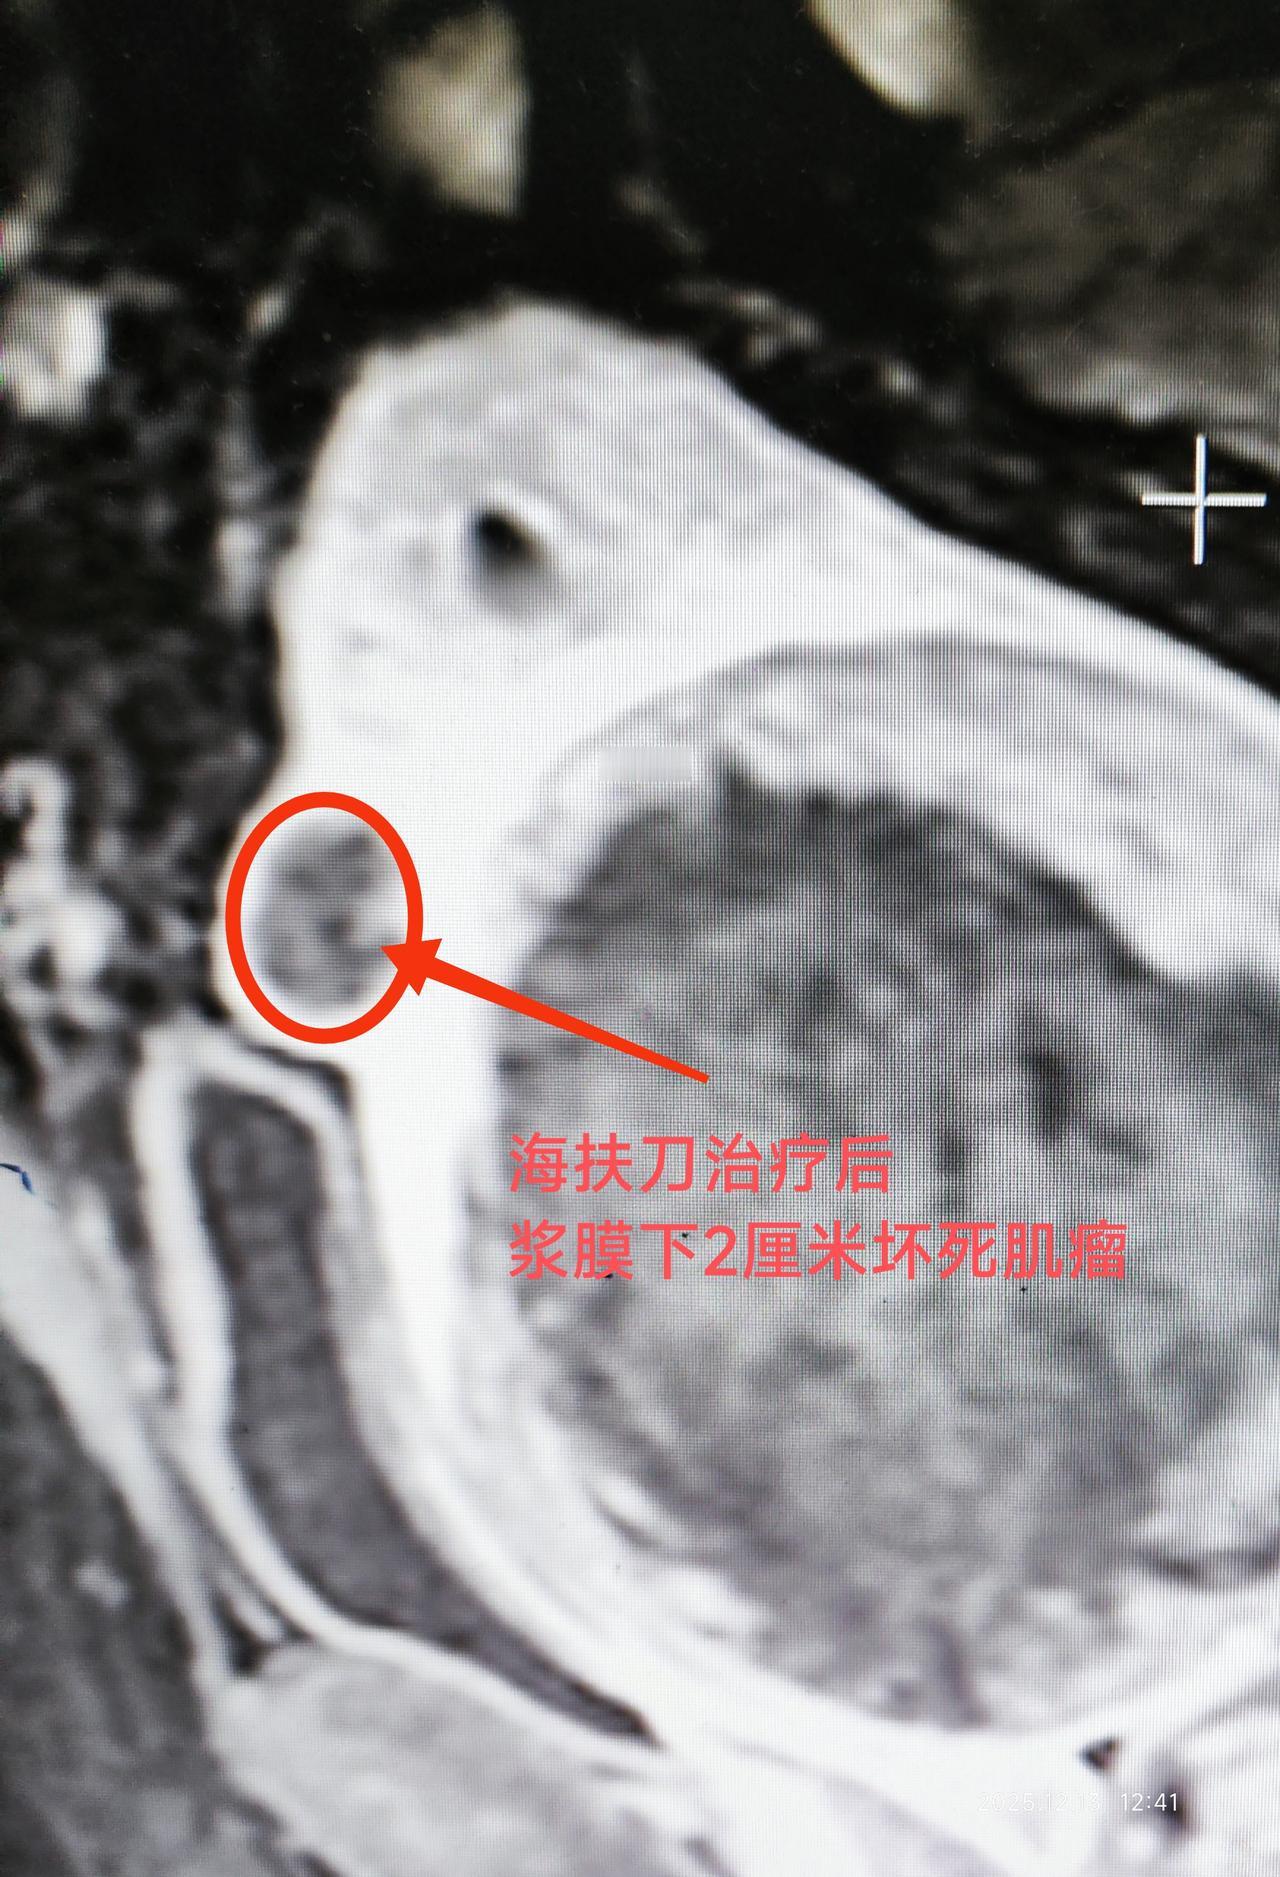

这是来自马来西亚子宫肌瘤患者,病人发现肌瘤十多年,当地建议手术切除,患者不愿意手术一直观察等待和中药治疗,现在肌瘤已经增大到9.5厘米,患者在医生同行那里了解到海扶可以无创消融肌瘤后,专门到我们中心进行治疗,术后复查显示肌瘤消融满意,对内膜也无损伤。子宫肌瘤 海扶刀